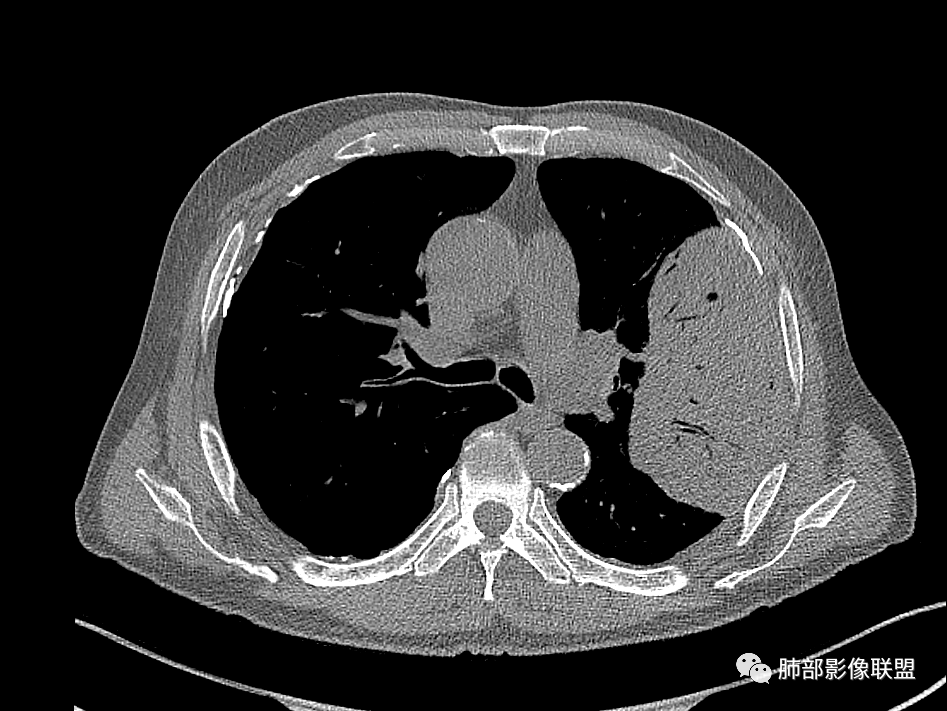

左肺上叶大肿块,膨胀性生长,边界清,密度较低,见部分坏死区,强化弱,肿块见支气管充气V扩张征,分布僵直,枯树枝特点,另一个重要特点血管造影征,淋巴瘤,肿块长轴与胸膜平行,与隐球菌鉴别,隐球荚膜抗原检查,明确诊断经皮肺穿刺。另胸膜钙化(问诊既往有无患胸膜炎病史)。

左肺上叶胸膜下肿块,宽基底与胸膜相连,跨叶裂,边缘清晰膨隆,其内支气管充气,部分扩张、僵直,无明显强化,血管造影征,考虑淋巴瘤,鉴别腺癌

左肺胸膜下巨大占位,跨叶裂,宽基底与胸膜相连,胸膜钙化,平扫密度较低,强化不明显,可见内部血管显影,支气管充气征和扩张,考虑为恶性,倾向于淋巴瘤

左侧胸腔巨大肿块,跨叶生长,临近胸膜钙化,边缘模糊,可见支气管影,定位肺内,增强后轻度强化,边缘见血管影,考虑淋巴瘤,鉴别肉瘤

左肺上叶胸膜下肿块,膨胀性生长,边界清晰,密度不均部分坏死,未见强化,病灶内支气管迂曲扩张,病灶长轴与胸膜平行,胸膜下脂肪间隙存在,胸膜钙化,考虑放线菌?毛霉?鉴别淋巴瘤

左肺上叶肿块,宽基底与胸膜相连,跨叶裂,边缘清晰膨隆,可见小分叶,其内支气管充气,部分扩张、僵直,呈枯枝征,支气管达边征,增强无明显强化,可见血管造影征,考虑恶性病变,淋巴瘤,鉴别粘液腺癌。

大肿块,边缘光滑,深分叶

近端支气管堵塞、推移为主

部分类似于脐凹征

内部支气管扩张

肺动脉推移为主,边缘部分进入

大肿块、表面光滑但深分叶,肺门侧支气管堵塞

1)部位:周围型或中央型软组织肿块,以周围型为多见,且肿瘤多位于肺上叶。如本例:该肿瘤位于左肺上叶。

2)大小及形态:由于本病恶性程度高,早期症状不明显,发现时肿块均较大。如本例病变巨大。

3)肿块边界和边缘:多较清楚,呈圆形、类圆形,且由于肿块生长速度不均匀,可见分叶,毛刺少见。有报道肿块周围毛玻璃影是多形性癌特征表现。

4)密度:肿块平扫为软组织密度,由于体积较大,内部常见大片状坏死,可出现不规则厚壁空洞或坏死内多发无壁小空洞,坏死多不均匀:坏死灶内可见如柳絮样的斑片样强化灶,坏死边缘与非坏死区分界不清本例坏死较明显,密度不均匀。

5)肿瘤强化方式:肺部恶性肿瘤强化程度与其血供丰富程度相关,血供丰富多强化明显,反之则较差。由于PSC 周边实性部分富血供及内部黏液变性、坏死,增强后肿块多数呈轻-中度边缘环形强化或不均匀小斑片状强化。国外学者对照病理发现肿瘤细胞或胶原组织增强扫描时强化,无强化的低密度区代表了黏液样变性区和出血坏死区。